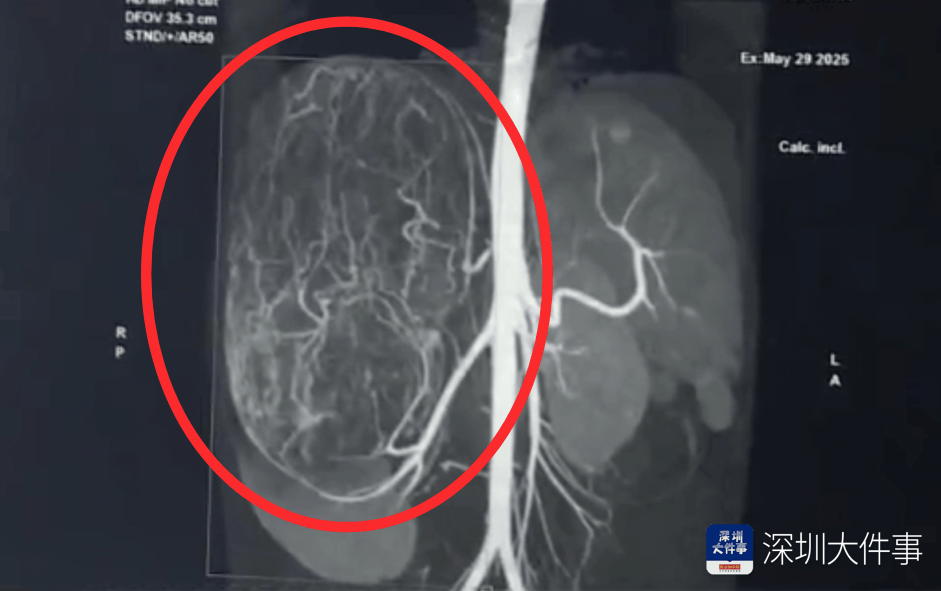

影像检查结果出来,所有人都倒吸一口冷气:一个直径27厘米(比篮球还大)的巨型肿瘤,霸占了整个腹腔右半边原油进口资质。肝脏被它硬生生挤到了肚脐眼以下的位置!

肿瘤体积过大,这也意味着留给医生的手术空间实在有限,强行微创?万一瘤子破了,肿瘤扩散大出血,后果不堪设想!所以,只能通过开放手术来做原油进口资质。

5月30日,医生为婷婷做手术,打开腹腔后,医生遇到了挑战:婷婷的肾动脉异于常人:正常人就1根肾动脉供血,她居然有3根原油进口资质。还有一支来自腹腔干动脉,一支来自腰动脉。

这三根“命脉”就盘踞在巨大的瘤体上,稍有不慎,剪错一根,就可能引发大出血原油进口资质。

手术团队屏气凝神,抽丝剥茧,一根一根精准找到、小心分离、稳稳阻断……经过3个多小时的精密操作:重达2.43公斤直径达27厘米的“巨无霸”肿瘤被完整端出原油进口资质。周围需要清扫的淋巴和脂肪组织也被清除。